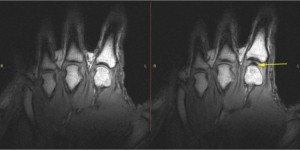

קנאק לאצבעות